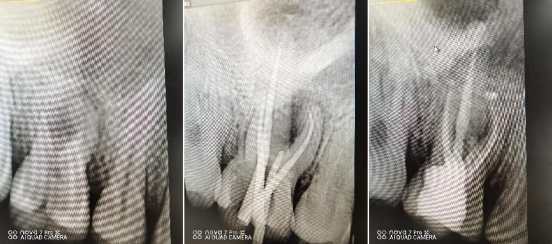

阻生牙微创拔除术